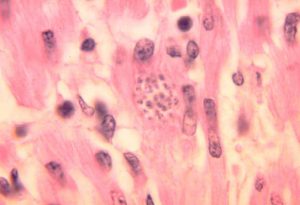

Die amastigote Form ist bis 4 Mikrometer lang, die Geißel ist fast unsichtbar.

In Säugetieren kommen die Parasiten als Trypomastigote im Blutstrom oder als Amastigote im inneren von Körperzellen vor. Nach der Infektion sind meist Makrophagen in der Haut das erste Ziel. Die intrazellulären Amastigoten können sich im Zytoplasma der Wirtszelle durch Teilung vermehren und nach erneuter Umwandlung in Trypomastigote die Wirtszelle zerstören. Damit gelangen sie wieder in die Blutbahn und können weitere Körperzellen des Wirbeltierwirtes, unter anderem Herzmuskelzellen, oder eine neue blutsaugende Raubwanze infizieren.